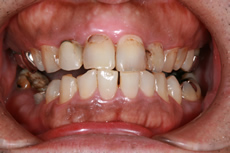

インプラント症例

術前